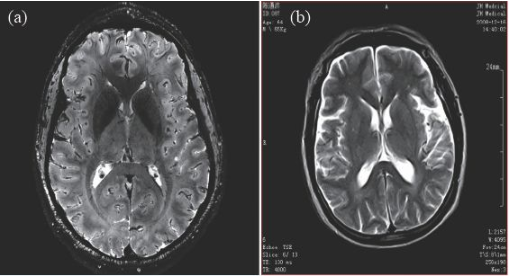

因(yin)此,磁(ci)(ci)(ci)(ci)共振(zhen)成像(xiang)技(ji)術目前的(de)發展趨勢,是朝(chao)著更高(gao)(gao)磁(ci)(ci)(ci)(ci)場(chang)(chang)強度發展,以期獲(huo)得更高(gao)(gao)分(fen)(fen)辨率的(de)圖像(xiang),并實現多核成像(xiang)。圖6 顯示了磁(ci)(ci)(ci)(ci)場(chang)(chang)強度的(de)高(gao)(gao)低對圖像(xiang)分(fen)(fen)辨率的(de)影像(xiang),(a)為7 T 磁(ci)(ci)(ci)(ci)場(chang)(chang)下的(de)圖像(xiang),(b)為0.35 T磁(ci)(ci)(ci)(ci)場(chang)(chang)下的(de)圖像(xiang),二(er)者的(de)圖像(xiang)分(fen)(fen)辨率可(ke)見一斑。

圖6 T2 加權成(cheng)像(xiang)(xiang)(a)7 T 下的成(cheng)像(xiang)(xiang),分辨(bian)率(lv)約0.3 mm;(b)0.35 T下的成(cheng)像(xiang)(xiang),分辨(bian)率(lv)約1 mm